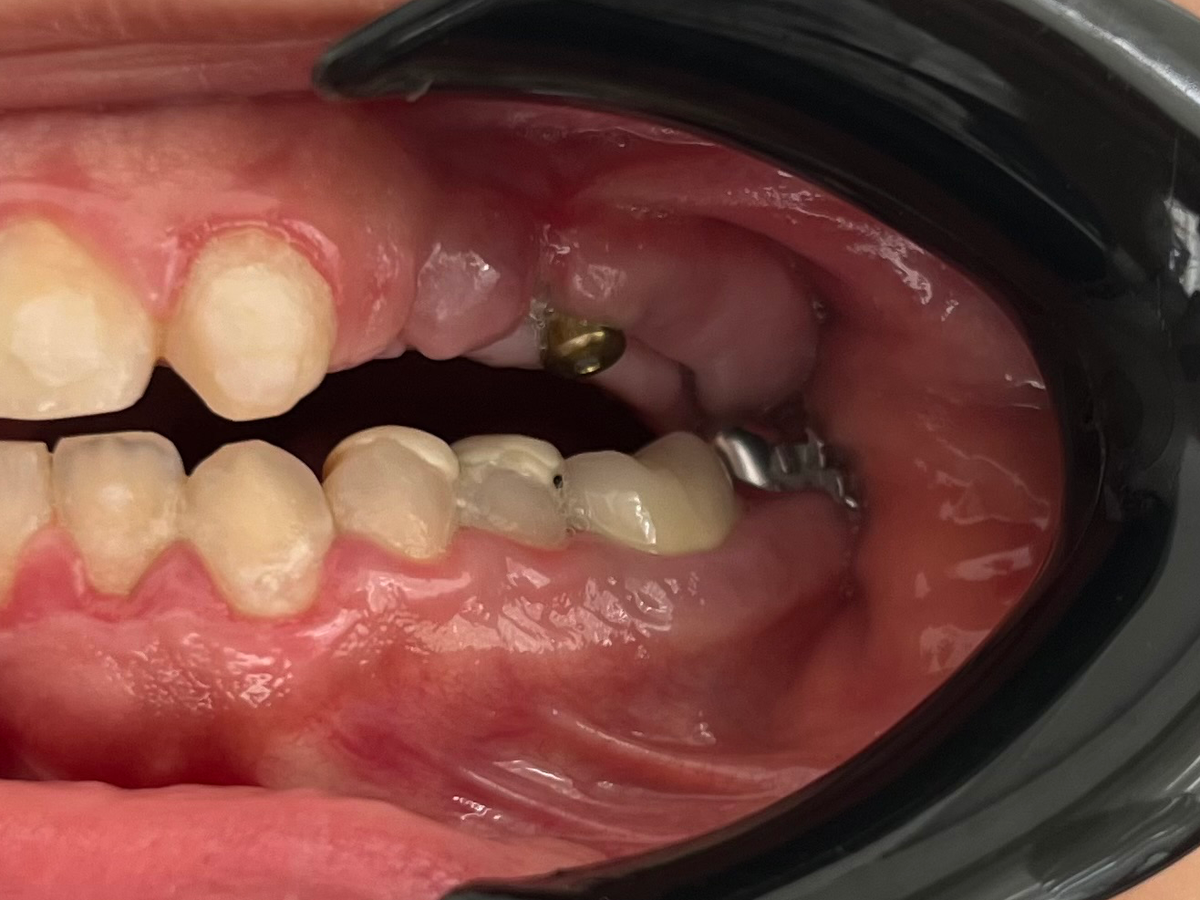

Because of my condition, I live with uncomfortable stress and struggle every day. I have already lost most of the back teeth in my upper jaw, which forces me to mouth-breathe and the dramatic loss has caused ongoing digestive problems, weight loss, and nutritional deficiencies. Chewing is extremely difficult, and even trying to fix small cavities has led to my teeth crumbling during treatment for unknown reasons. Beyond the physical pain, my confidence has been deeply affected—I no longer feel comfortable smiling or speaking freely, and simple joys like eating a meal or laughing with friends have become painful reminders of what I have lost.

Several years ago, I went through a surgery in hopes of ending this struggle, but it ended in tragedy. The dentist performed the procedure carelessly, leaving both of my jaws misshaped and my implants misplaced. To make things worse, i couldn’t reach out to him and receive the missing parts of my implants to continue my treatment . After spending what I had on that failed procedure, I was left not only with greater health problems but also a heavy financial burden. For years I visited doctors, but many rejected my case due to its complexity.